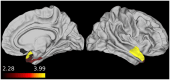

Results: All registration methods demonstrated significant hypoperfusion in frontal and temporal regions in each patient group relative to controls. All registration methods detected hypoperfusion in the left insular cortex, middle temporal gyrus, and temporal pole in sFTLD-TDP relative to sFTLD-tau. FTLD-CDR had an inverse association with CBF in right temporal and orbitofrontal ROIs in sFTLD-TDP. Manual+BBR performed similarly to FLIRT+BBR.